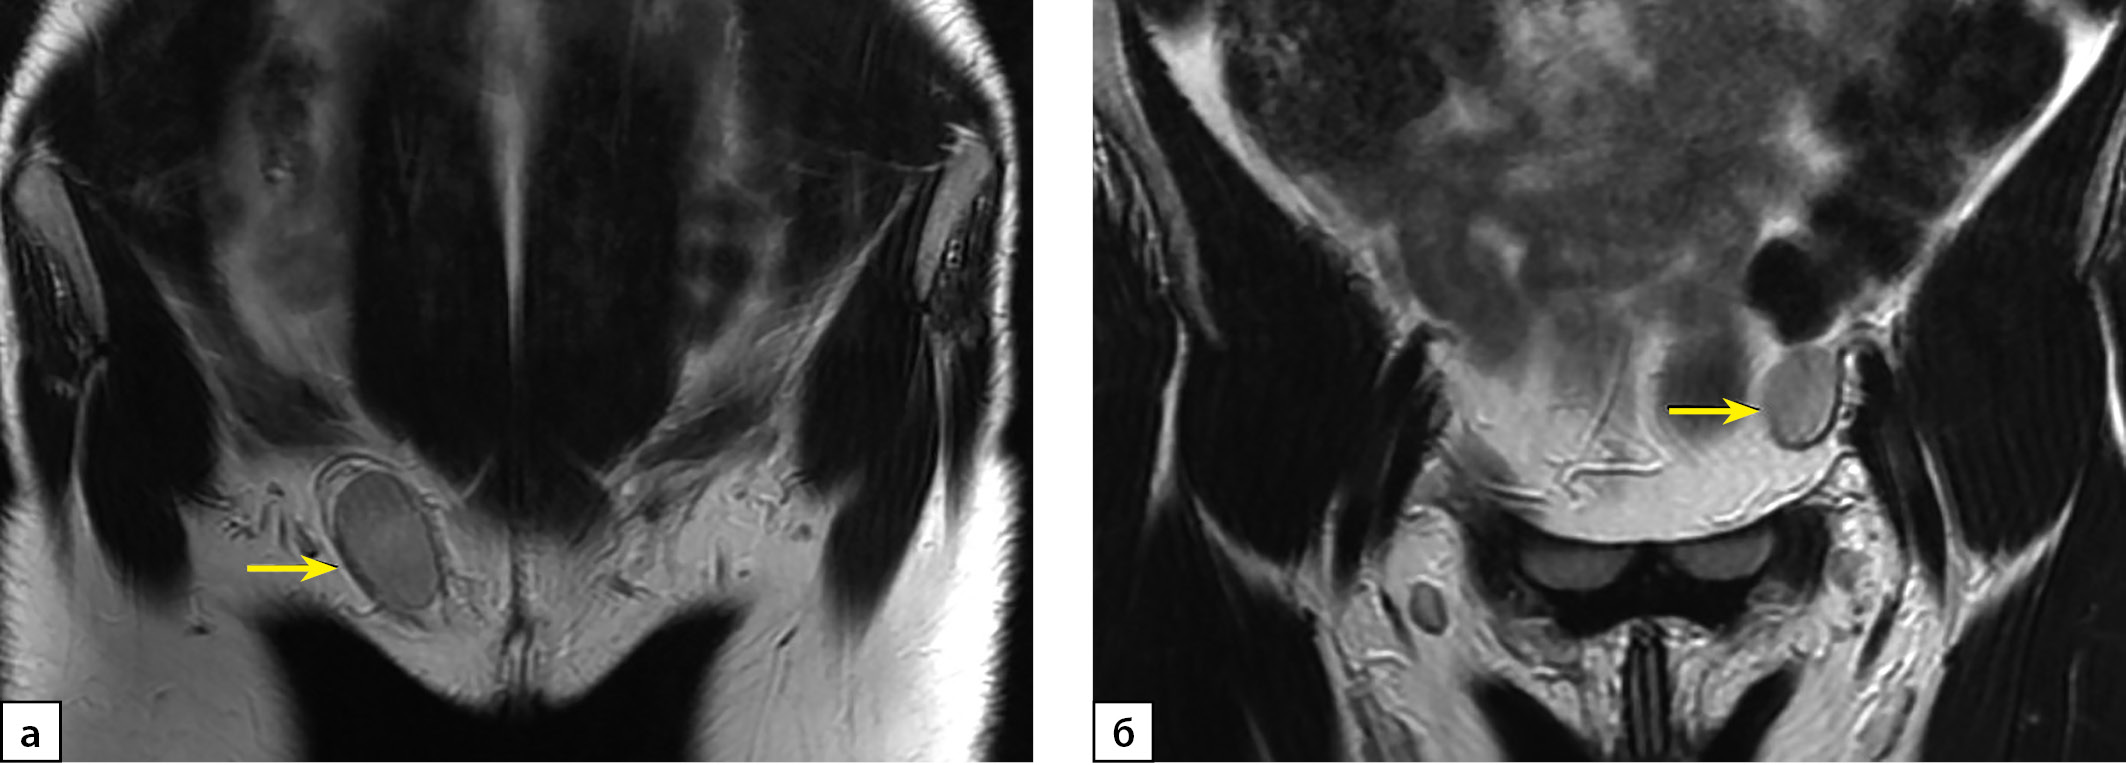

Рисунок 4. МРТ органов малого таза пациентки Х, Т2 ВИ, сагиттальная плоскость.

Примечание: Гипоплазированная ткань предстательной железы (стрелка).

Figure 4. MRI of the patient X pelvis, T2-WI, saggital plane.

Note: prostate hypoplasia (arrow).